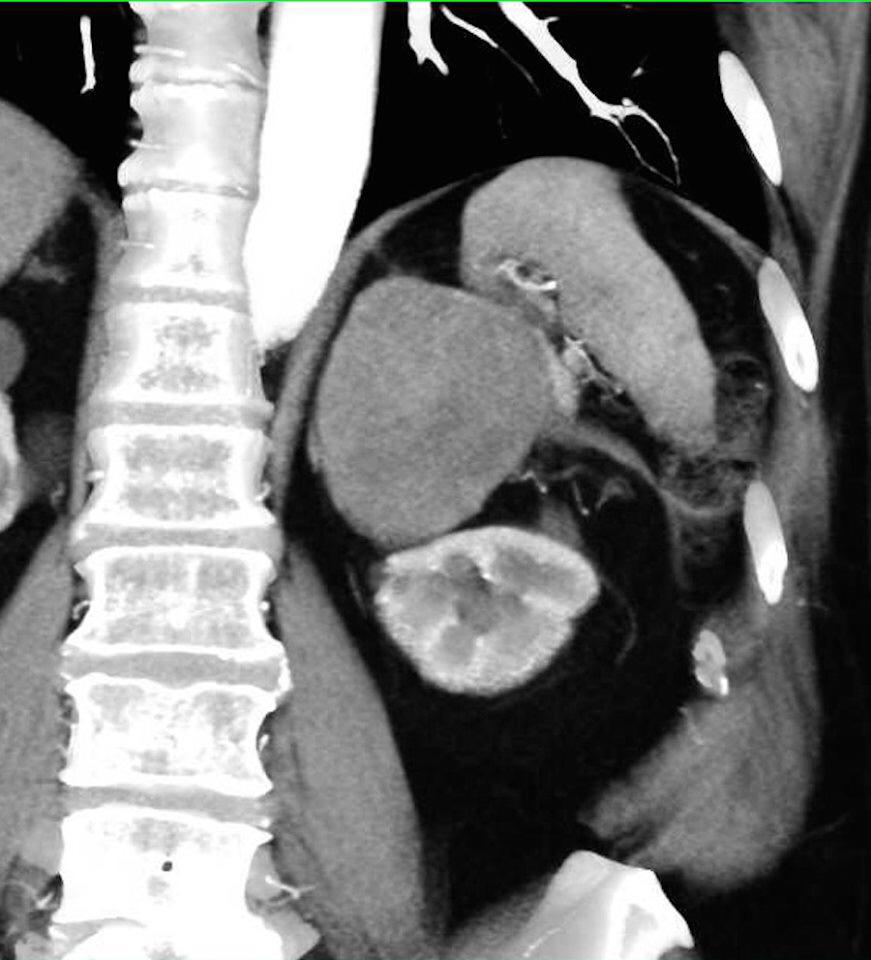

La hemorragia suprarrenal es una entidad infrecuente que puede ser uní o bilateral.

Cuando es unilateral suele ser clínicamente silente y en la mayor parte de los casos se diagnostica de forma incidental.

Sin embargo, la hemorragia bilateral por lo general desencadena una insuficiencia suprarrenal aguda, a veces dando como resultado el coma o la muerte si la terapia de reemplazo de esteroides no se administra con prontitud.

Las causas de hemorragia suprarrenal se dividen en traumáticas (la mayoría unilaterales y derechas) y espontaneas, agudas y crónicas.